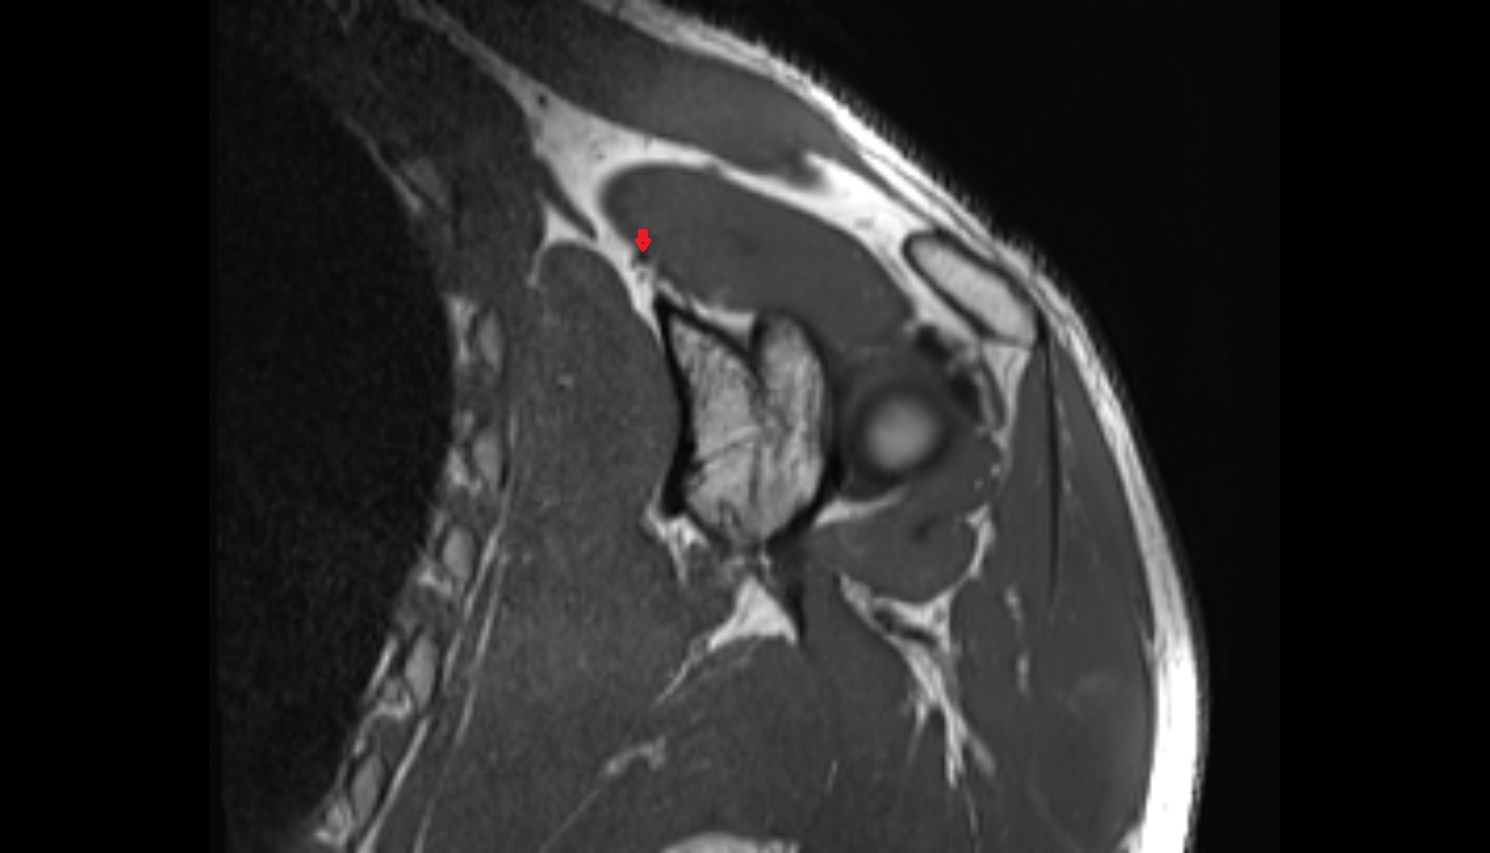

- Temporomandibular joint

- Articular disc of temporomandibular joint

- Mandibular condyle

- Mandibular fossa

- Superior retrodiscal layer

- Intermediate zone of articular disc